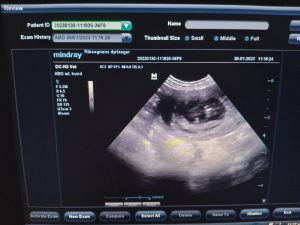

Olympia wurde am 30. januar gescannt mit ungefähr 7 welpen.